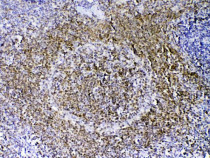

ARG41677 anti-PAX5 antibody IHC-P image

Immunohistochemistry: Paraffin-embedded Mouse spleen tissue. Antigen Retrieval: Heat mediation was performed in Citrate buffer (pH 6.0, epitope retrieval solution) for 20 min. The tissue section was blocked with 10% goat serum. The tissue section was then stained with ARG41677 anti-PAX5 antibody at 1 µg/ml dilution, overnight at 4°C.